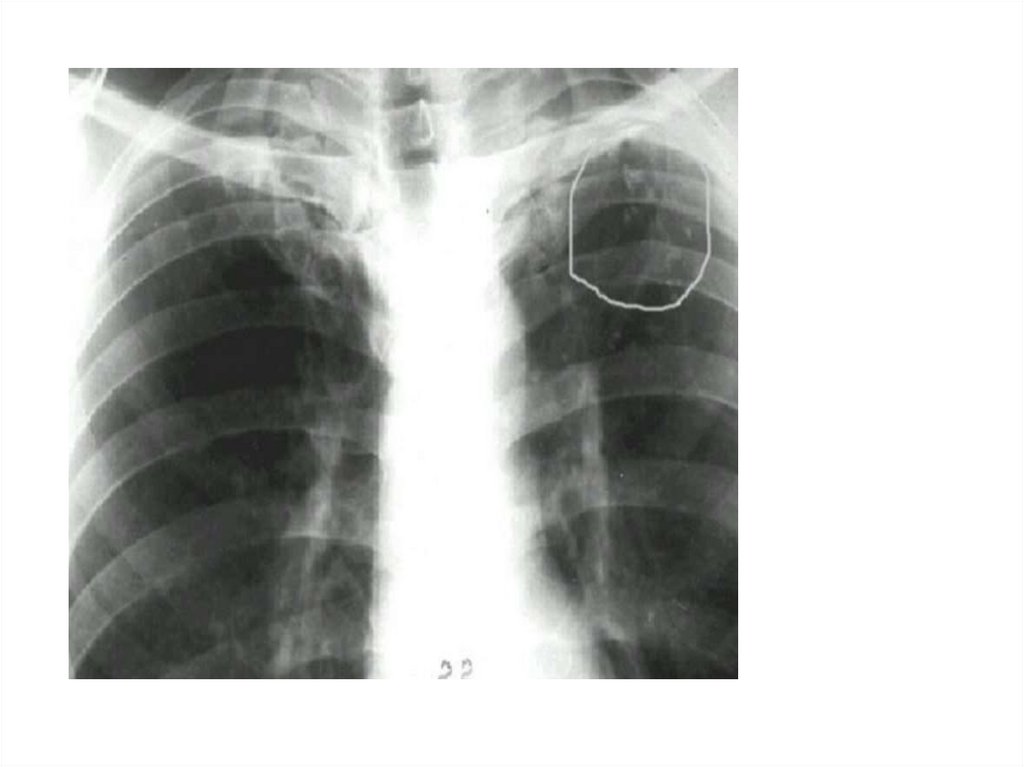

Рентгенограмма № 4

33. Рентгенограмма № 4